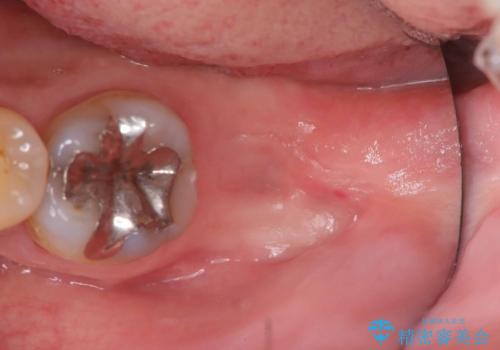

検査の結果、左下7番は歯周ポケットが8mmと深く、レントゲンでも根尖部から骨が溶けている状態が確認されました。エンドペリオ病変と診断し、精密根管治療による保存か、抜歯をしてインプラントで治療するかをご提案したところ、患者様は抜歯・インプラント治療を希望されました。

インプラントとセラミック治療を組み合わせることで、見た目も自然で噛み心地の良い状態を回復することができ、患者様にも大変ご満足いただけました。